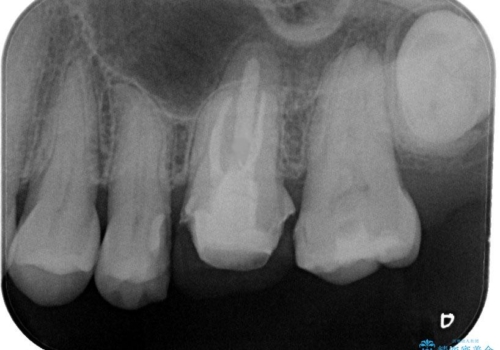

金属をセラミックにしたい、根管治療も行ったケース

左上6の金属のかぶせものをセラミックにかえるにあたり、根管治療からやり直しています。

基礎工事と同じで、歯の治療においても見えるところを白くきれいにするだけではなく、根管治療をしっかり行うこともとても大切です。